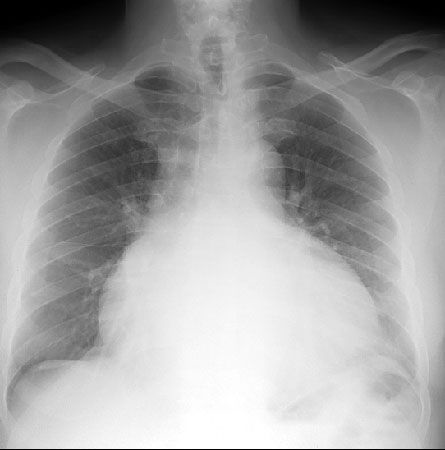

• Рентгенография грудной клетки.

• Эхокардиография: выпот, утолщение перикарда.

• Выпот (>15–35 мл), сепарация эпикарда и перикарда >1 мм в диастолу.

• Величина выпота: малый (сепарация • Утолщение (>3–4 мм) и кальцификация перикарда (констриктивный перикардит).